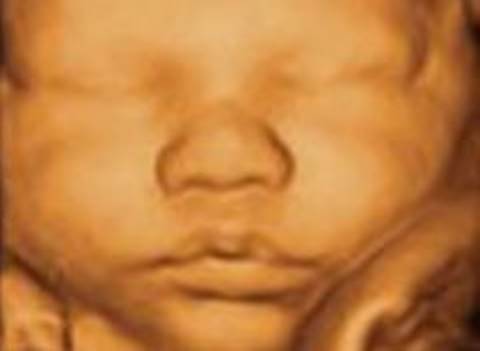

And during the third stage (from the 8th week until birth), the embryo has become a fetus, and its facial and bodily structures have begun to be immaculately shaped (Figure-1).

Jaw and facial development occur during the 4-12 weeks in the womb. By the end of the 10th week, the face can be seen with an ultrasonographic examination.

Figure-1: Ultrasonographic image of the facial region of a fetus in the mothers womb.